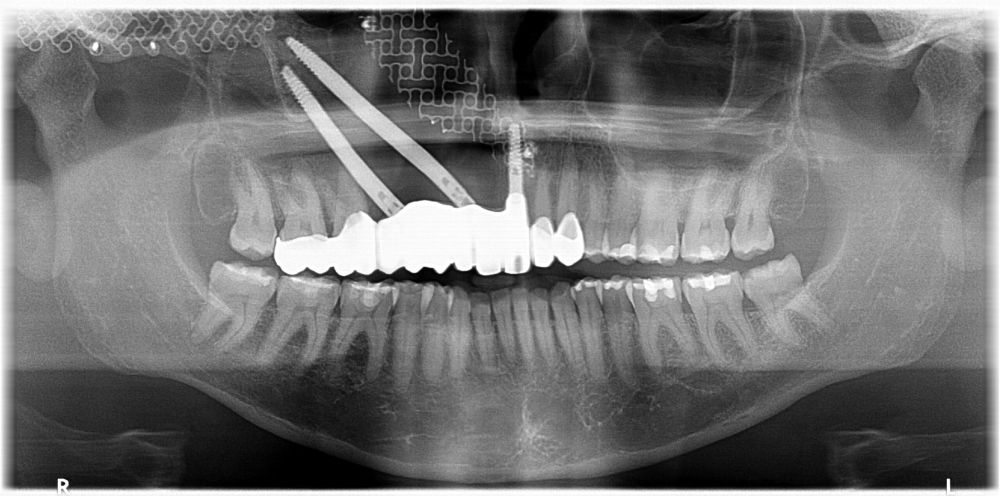

Presentamos el caso de una paciente de 47 años que acude al servicio de cirugía maxilofacial por dolor en el área sinusal derecha en Junio de 2020. Se realizó una radiografía panorámica en la que se observó una imagen sospechosa en la zona del primer cuadrante. Dichos hallazgos se confirmaron con la realización de una tomografía axial computarizada (TAC) facial y una resonancia magnética en las que se identifica una extensa lesión tumoral que ocupaba el seno maxilar derecho e infiltraba el suelo de la órbita derecha y fosa nasal derecha (Figuras 1, 2 y 3). Tras la realización de una biopsia, se confirmó la presencia de un carcinoma adenoide quístico. De este modo, se planificó la extirpación quirúrgica y la fijación mediante placas preformadas sobre un modelo impreso en poliamida (Figura 4).

Bajo anestesia general, se realizó la resección quirúrgica junto con la fijación de dos placas preformadas y colocación simultánea de dos implantes cigomáticos y un implante endoóseo en posición del 2.1 (Figuras 5 y 6). Debido a la presencia de márgenes quirúrgicos comprometidos en el informe anatomopatológico, se indicó la administración de radioterapia adyuvante. Por este motivo, se decidió realizar un puente provisional dentosoportado de 1.7 a 2.3 (Figura 7) para mejorar la situación estética y funcional de la paciente durante todo el proceso y evitar un colapso de los tejidos blandos por la radioterapia. Para ello, se tallaron los molares (1.7, 1.6) e incisivo lateral y canino (2.2, 2.3), y se fabricó un puente fresado en polimetilmetacrilato (PMMA) con refuerzo metálico (Figuras 8 y 9).

Una vez finalizada la radioterapia, la paciente se encontraba libre de enfermedad. Por lo que se procedió a la restauración definitiva implantosoportada. Tras la segunda fase, se colocaron dos pilares transepiteliales Multiunit Ò rectos y un pilar Multunit Ò angulado de 17º (Figura 10).

Finalizado el tratamiento oncológico y confirmada la ausencia de enfermedad activa, se procedió a la segunda fase quirúrgica con la colocación de pilares transepiteliales Multiunit®. La integración de los implantes cigomáticos y del implante endoóseo fue satisfactoria, observándose estabilidad clínica y ausencia de signos de periimplantitis.